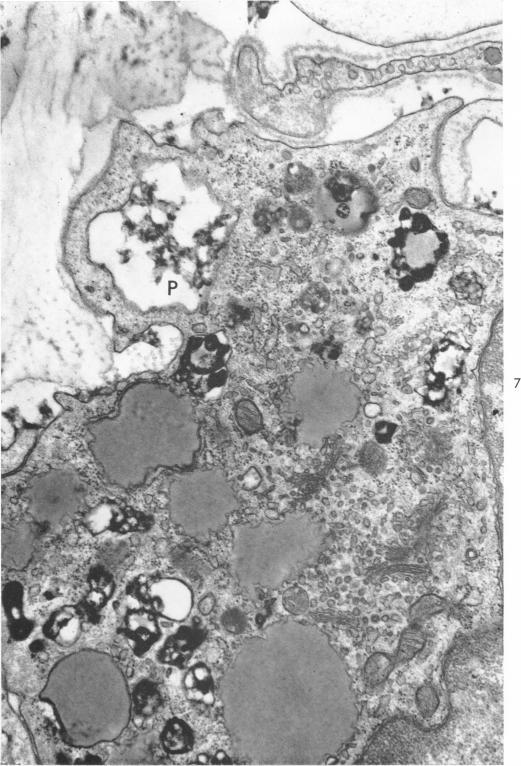

GEER J C

Am J Pathol. 1965 Aug;47(2):241-69.